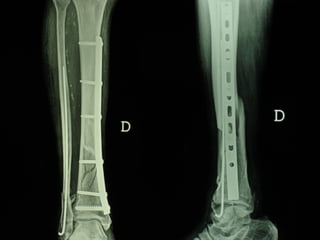

Dal Gennaio 2000 al Febbraio 2006 abbiamo trattato 167 fratture chiuse  con placca percutanea  in 164 pazienti :  27 lesioni diafisarie di gamba, 12 piloni tibiali ,  11 fratture prossimali di tibia, 36 fratture sovracondiloidee di femore, 17 fratture diafisarie di femore, 43 fratture metaepifisarie prossimali di omero, 21 diafisarie d’omero.  156 guarigioni 8 fallimenti

I buoni risultati ottenuti dipendono da 5 punti fondamentali:   una accurata riduzione percutanea della frattura  precise vie di accesso  l’utilizzo della placca che consenta il più lungo braccio di leva possibile il pretensionamento della placca  una sintesi con un ridotto numero di viti

Precise vie di accesso

Placche lunghe e pretensionate

Placche lunghe e pretensionate Sintesi con un ridotto numero di viti